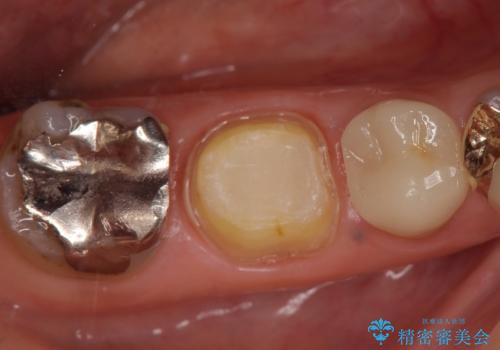

診査の結果右下6の歯の神経が死んでいたため、根管治療を行いました。

その後症状の消失を確認し、オールセラミッククラウンによる補綴を行いました。

今回用いたオールセラミッククラウンはジルコニアフレームという白い素材の上にセラミックを盛っているため、審美性が非常に高いのが特徴です。